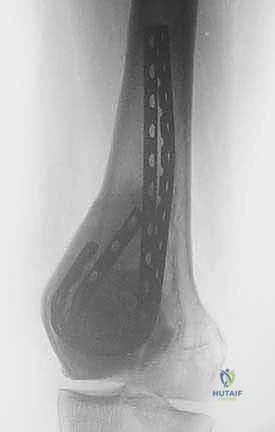

الخطوة الخامسة: إعادة البناء والترميم (Reconstruction)

بعد القضاء على الورم، يتبقى تجويف فارغ داخل العظم. يقوم الدكتور هطيف بملء هذا الفراغ إما باستخدام ترقيع عظمي (Bone Graft) أو الإسمنت العظمي (PMMA - Bone Cement). الإسمنت العظمي له فائدة مزدوجة: فهو يوفر دعماً ميكانيكياً فورياً للعظم، والحرارة الناتجة عن تصلبه توفر تأثيراً إضافياً قاتلاً للخلايا الورمية المتبقية.